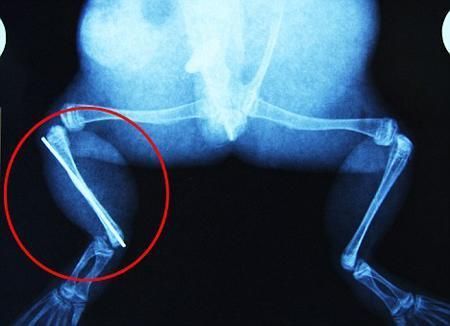

環(huán)球網(wǎng)4月2日?qǐng)?bào)道 據(jù)《每日郵報(bào)》報(bào)道,上個(gè)月,南非大牛蛙布魯萊的右小腿被鄰居家的一只狗咬到,導(dǎo)致粉碎性骨折,現(xiàn)在經(jīng)過(guò)2個(gè)小時(shí)的手術(shù),它的斷腿已經(jīng)被接上,它也因此成為有史以來(lái)第一只通過(guò)外科手術(shù)用鋼針接上斷腿的青蛙。

野生生物專家安妮經(jīng)常為學(xué)校寫(xiě)教材,她認(rèn)為這是人類第一次通過(guò)手術(shù)給一只青蛙接斷腿。在手術(shù)開(kāi)始階段,獸醫(yī)把少量給狗用的麻醉藥注入到這只青蛙體內(nèi),讓它失去知覺(jué)。然后他在布魯萊的斷腿上切開(kāi)一個(gè)小口,把一根小鋼針植入腿里。最后獸醫(yī)給它縫了9針,把切口縫合在一起。僅僅幾周后,布魯萊就能在安妮家附近活動(dòng)了。這只青蛙大約已有25歲,主要以嚙齒動(dòng)物、蛇和其他青蛙為食。布魯萊所屬的牛蛙種群正在不斷減小,目前只能在非洲南部的濕地里才能看到這種青蛙。

安妮有2個(gè)孩子,她已經(jīng)從事20多年兩棲動(dòng)物保護(hù)工作。她認(rèn)為鄰居家的狗狗在把布魯萊從地下刨出來(lái)的時(shí)候,它正在地下冬眠、她說(shuō):“世界上只有這個(gè)地區(qū)能看到這種牛蛙,這種青蛙現(xiàn)在變得越來(lái)越稀少。因?yàn)槲覐氖乱吧锉Wo(hù)工作,因此認(rèn)識(shí)很多兩棲動(dòng)物專家,但是以前他們誰(shuí)也沒(méi)見(jiàn)過(guò)這種事情?吹讲剪斎R越來(lái)越健康我非常開(kāi)心,F(xiàn)在還需要一段時(shí)間,它的金屬腿和它的骨骼才能融為一體,那時(shí)布魯萊會(huì)跟以前一樣健康。我們認(rèn)為這個(gè)過(guò)程需要幾周時(shí)間,但是一旦它完全康復(fù),我希望把它放歸大自然,讓它重新回到它最鐘愛(ài)的濕地里。”